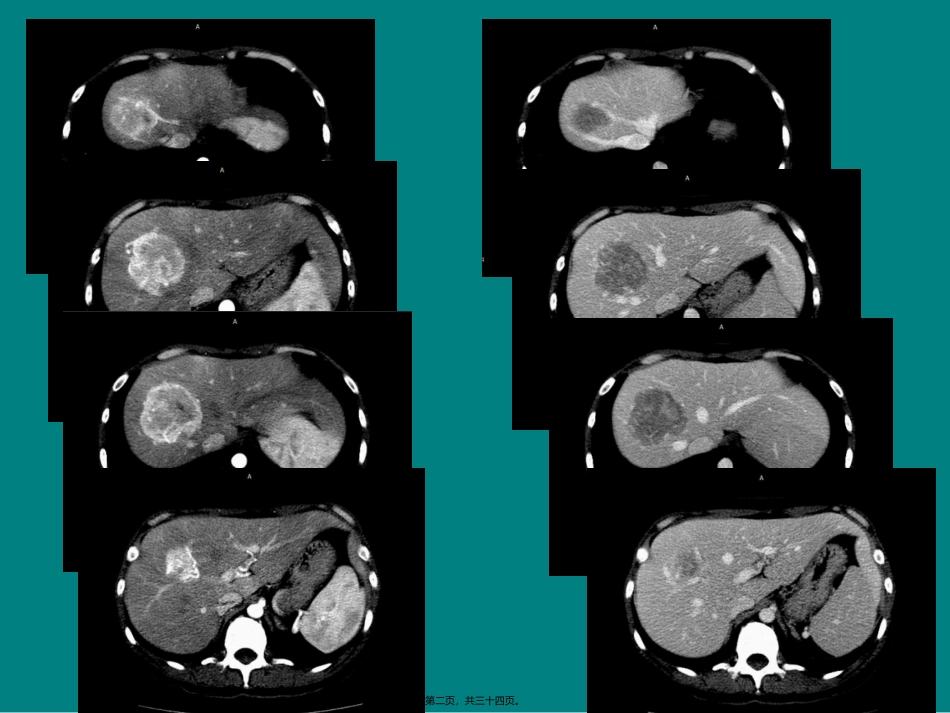

第一页,共三十四页。第二页,共三十四页。第三页,共三十四页。第四页,共三十四页。第五页,共三十四页。病理:炎性肌纤维母细胞瘤〔IMT〕第六页,共三十四页。炎性肌纤维母细胞瘤〔IMT〕2002年,WHO定义:“由分化的肌纤维母细胞性梭形细胞组成,常伴大量浆细胞和/或淋巴细胞的一种间叶性肿瘤〞〔注:肌纤维母细胞是结缔组织再生或增生过程中一个重要的过渡细胞,在超微结构上兼有成纤维细胞和平滑肌细胞两者的特征,可分化为平滑肌细胞及纤维细胞〕IMT是一种少见独特的间叶性肿瘤,病因尚不清楚,多认为与感染、免疫及过敏等因素有关。多发生在四肢、头颈及躯干的真皮层内,儿童多见于肺。少数见于肌肉、腹腔、腹膜后及腹股沟等处。发生于肝脏罕见。现已证实炎性肌纤维母细胞瘤为低度恶性肿瘤,属交界性(偶有转移性)的间叶组织肿瘤。第七页,共三十四页。HIMT•年龄:35~47岁•男女比例:3:1•部位:多位于右半肝,偶见于左半肝,大多接近于肝外表•临床表现:大局部病人起病隐匿,其临床表现包括低热、右上腹隐痛、腹部肿块•实验室检查:CRP增高,血沉加快,AFP及CEA正常•病理表现:大体:实质性、无包膜,组织切面呈灰白色或黄色;镜下:瘤组织主要由梭形细胞组成,排列紊乱,局部呈编织席纹状,瘤细胞胞质丰富,嗜酸性,但核分裂象少见,肿瘤间质内玻璃样胶原纤维束密集交错,间隙内有大量的淋巴细胞、浆细胞或嗜酸性粒细胞浸润。第八页,共三十四页。炎性假瘤与炎性肌纤维母细胞瘤•文献报道肝“炎性假瘤〞,属于肝细胞坏死后炎性增生。肝炎性假瘤肿块呈土黄色或灰白色,有较厚完整纤维包膜,镜下病灶内常见凝固性肝组织坏死,周围为增生的胶原纤维条带伴各种炎性细胞浸润,并有典型的分层特征。•而肝IMT较罕见,肿块大体边界清楚,但缺乏包膜,无肝组织坏死。第九页,共三十四页。⑴黏液样/血管型:以黏液、血管、炎症区域为主;⑵丰富梭形细胞型:梭形细胞夹杂炎性细胞.类似纤维组织细胞瘤,当累及胃肠道时。常被误认为平滑肌瘤或间质瘤;⑶少细胞纤维型:致密成片的胶原纤维可类似瘢痕或硬化性纤维瘤,少局部病例出现点状或大片的钙化和化生骨。IMT第十页,共三十四页。炎性假瘤•①以浆细胞为主者称为浆细胞性肉芽肿;•②以组织细胞占优势者称为黄色肉芽肿;•③以弥漫致密纤维组织增生为主的称为硬化性假瘤。第十一页,共三十四页。影像学表现HIMT的影像表现充分反映其病理特点,病灶内不同程度纤维组织增生、炎细胞浸润、凝固性坏死及间质血管增生是HIMT影像表现多样化的病理根底。病灶形态多数呈圆形或类圆形,无包膜,边界清楚,CT平扫呈低或稍低密度,密度可不均匀,低密度区为浸润的慢性炎性细胞或坏死,相对高密度区为增生的纤维母细胞。第十二页,共三十四页。•增强于动脉期显示均匀/不均匀明显/不明显强化,门脉期和实质期持续强化。•病灶不强化或强化不明显者,病理常表现为凝固性坏死灶或纤维,少量炎性细胞浸润;强化明显者,病理上常见较多肿瘤细胞、粘液及丰富的增生血管,所以HIMT在增强CT上常无确定的特征性表现。第十三页,共三十四页。PEI/CTSUVmax没有鉴别IMT与恶性肿瘤的价值。SUVmax的大小主要取决于肿瘤细胞的密度、肿瘤细胞的异型性、炎性细胞的密度及其活化程度。第十四页,共三十四页。黏液样/血管型第十五页,共三十四页。第十六页,共三十四页。少细胞纤维型第十七页,共三十四页。第十八页,共三十四页。丰富梭形细胞型第十九页,共三十四页。鉴别诊断第二十页,共三十四页。第二十一页,共三十四页。供血与引流血管FNH:供血:粗大不规那么肝动脉引流:肝静脉肝癌:供血:粗大不规那么肝动脉引流:绝大局部门脉,1.8%肝静脉第二十二页,共三十四页。FNH第二十三页,共三十四页。第二十四页,共三十四页。HCC第二十五页,共三十四页。瘢痕第二十六页,共三十四页。瘢痕常见:FNH、血管瘤、肝细胞肝癌〔纤维板层型〕罕见:肝转移瘤、肝胆管细胞癌第二十七页,共三十四页。第二十八页,共三十四页。第二十九页,共三十四页。肾癌转移第三十页,共三十四页。第三十一页,共三十四页。第三十二页,共三十四页。富血供第三十三页,...

1、当您付费下载文档后,您只拥有了使用权限,并不意味着购买了版权,文档只能用于自身使用,不得用于其他商业用途(如 [转卖]进行直接盈利或[编辑后售卖]进行间接盈利)。

2、本站所有内容均由合作方或网友上传,本站不对文档的完整性、权威性及其观点立场正确性做任何保证或承诺!文档内容仅供研究参考,付费前请自行鉴别。